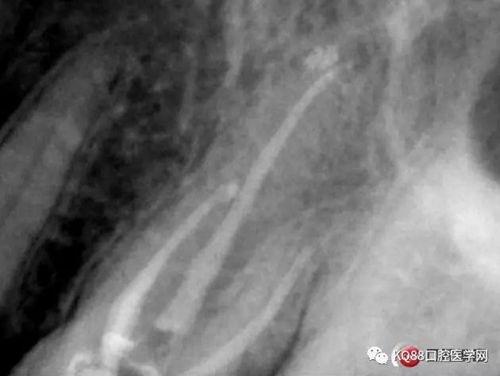

一個(gè)上6,常規(guī)的拍片,同上面的方法,根管口定位,乍一看三個(gè)根管,但是仔細(xì)研究,發(fā)現(xiàn)近中頰根,兩個(gè)根管口的C型根管,心理明了以后開(kāi)始常規(guī)操作。

第一開(kāi)髓后,只看見(jiàn)三個(gè)根管,于是進(jìn)行三個(gè)根管的預(yù)備,然后按照髓底解剖圖,進(jìn)行Mb2探查,近中頰根與腭根連線,遠(yuǎn)中頰根向其做垂直線,一般都在這條線附近,于是我開(kāi)始去髓底白色鈣化,終于找到了Mb2,有鈣化,但是疏通后,到達(dá)根方,于是拍攝插針片。

四個(gè)根管成型,只是近中兩個(gè)根管融合為一個(gè),典型的C型根管。最后開(kāi)始根充,射片。